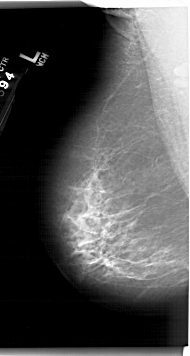

A_1411_1.LEFT_MLO

LEFT_MLO LINES 6751 PIXELS_PER_LINE 3601 BITS_PER_PIXEL 12 RESOLUTION 43.5 NON_OVERLAY